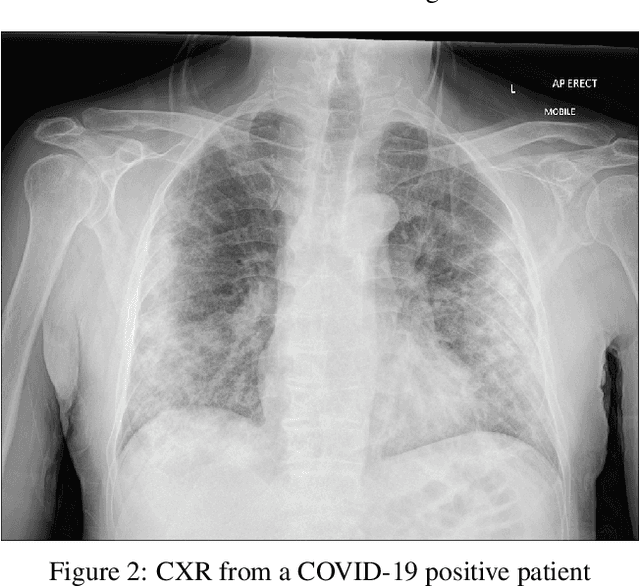

One of the primary clinical observations for screening the infectious by the novel coronavirus is capturing a chest x-ray image. In most of the patients, a chest x-ray contains abnormalities, such as consolidation, which are the results of COVID-19 viral pneumonia. In this study, research is conducted on efficiently detecting imaging features of this type of pneumonia using deep convolutional neural networks in a large dataset. It is demonstrated that simple models, alongside the majority of pretrained networks in the literature, focus on irrelevant features for decision-making. In this paper, numerous chest x-ray images from various sources are collected, and the largest publicly accessible dataset is prepared. Finally, using the transfer learning paradigm, the well-known CheXNet model is utilized for developing COVID-CXNet. This powerful model is capable of detecting the novel coronavirus pneumonia based on relevant and meaningful features with precise localization. COVID-CXNet is a step towards a fully automated and robust COVID-19 detection system.